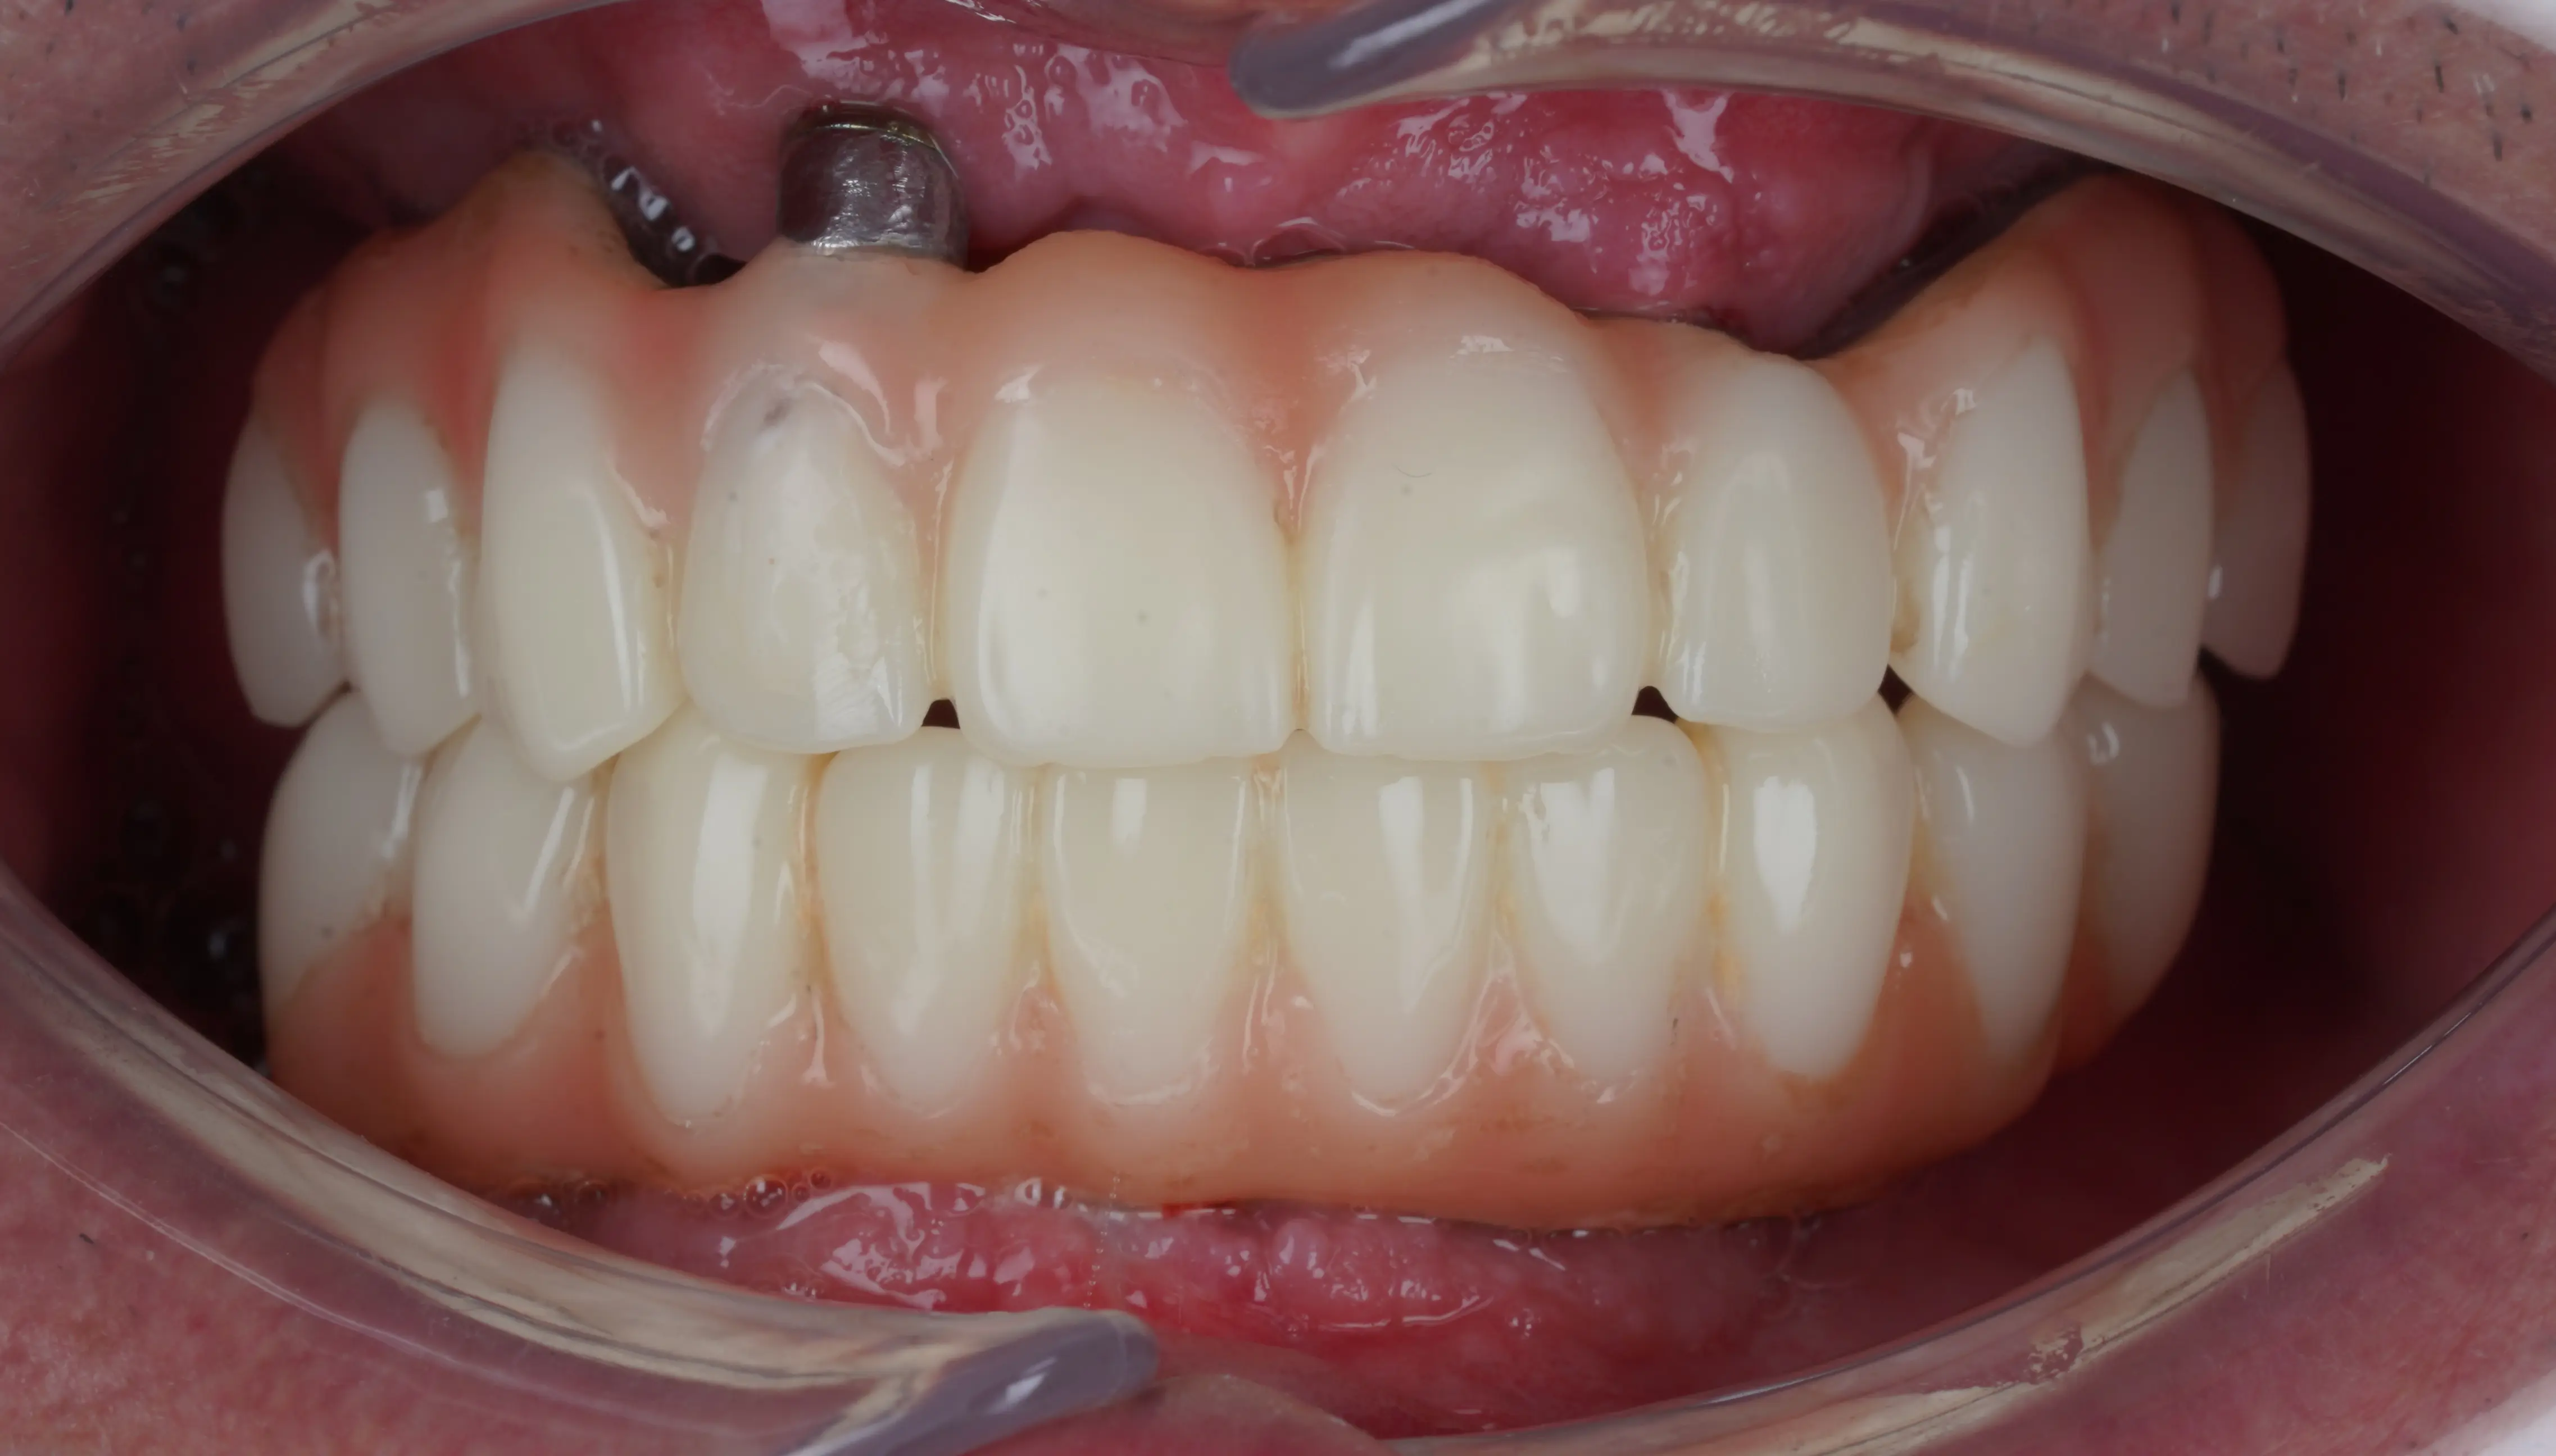

Aceeași proteză, după 6 luni

(se poate observa gingia cum s-a retras)

Proteza dentară definitivă se montează după perioada de vindecare și osteointegrare, în general la 6–8 luni de la intervenție.